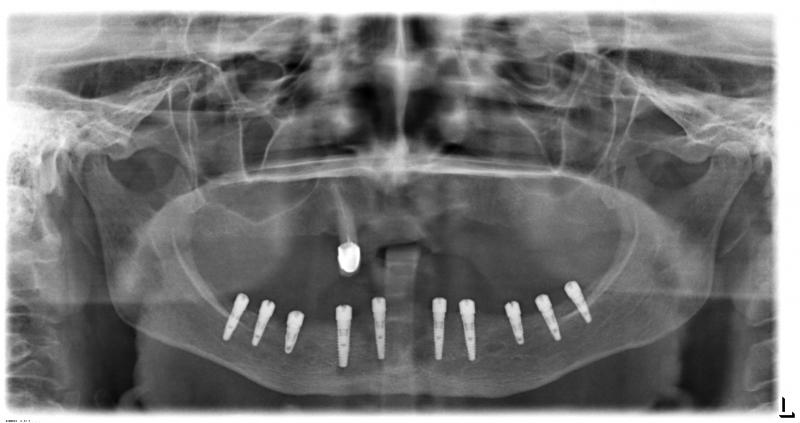

Установка 10 имплантантов на беззубую челюсть с помощью компьютерной программы: Через месяц после удаления

Через месяц после удаления